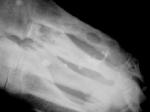

На рентгенограммах левой стопы (Рис. 2, 3, 4)в различных костях(преимущественно 5, 4 и 3 пальцы) определяются участки разрежения костной ткани округлой формы диаметром от 2-3 мм до 7-8 мм, окруженных склеротическим валом. Кости фаланги пятого пальца значительно деформированы.